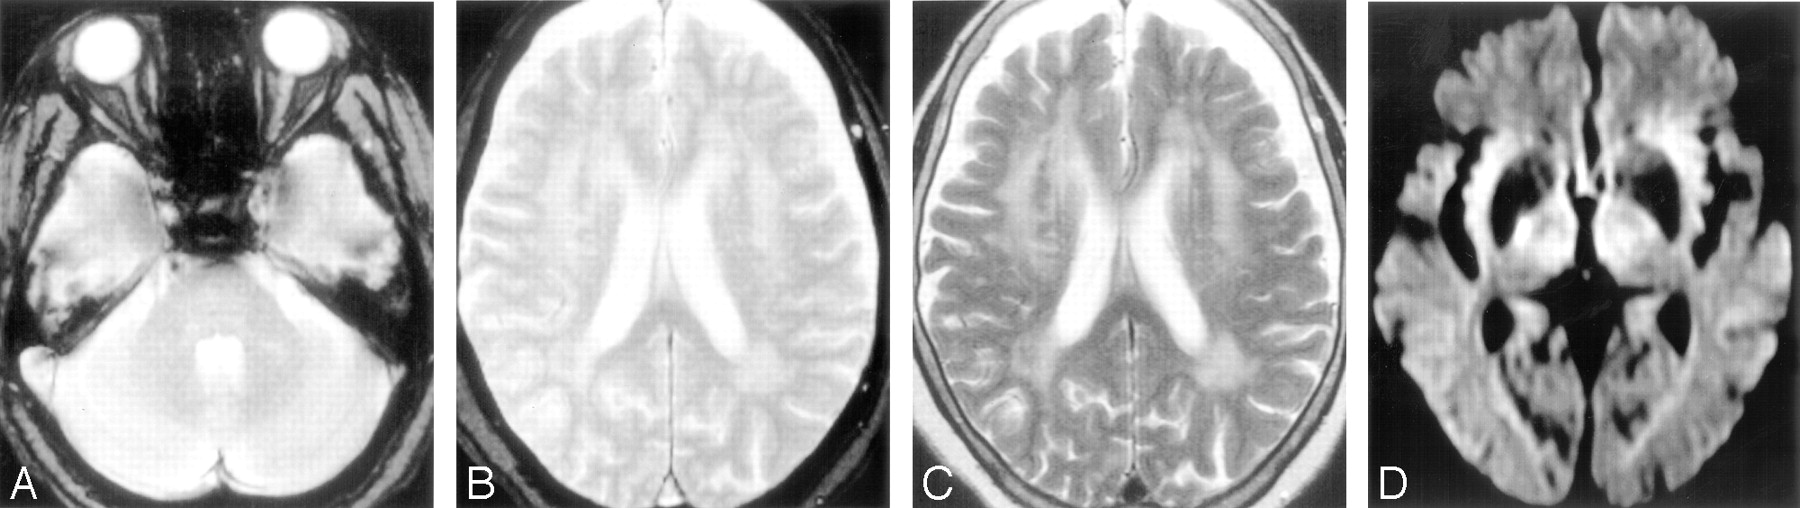

The mean follow-up period was 564.8 ± 220.5 days. Three patients were lost to follow-up (2 patients in group C and 1 patient in group D), and 1 patient in group B died of a cause not related to stroke. During the follow-up period, 26 patients developed recurrent strokes, including 10 intracerebral hemorrhages and 16 ischemic strokes. Representative MR and CT images of patients with recurrent stroke are shown in Figs 1 and 2. Frequencies of the development of overall recurrent stroke, intracerebral hemorrhage, and ischemic stroke are shown in Table 2, Table 3, and Table 4, respectively. Development of intracerebral hemorrhage was the most frequently observed in patients of group D (19.0%). Analysis by the Kaplan-Meier method showed that the estimated recurrence rate of intracerebral hemorrhage was also the highest in patients in group D. The frequency of development of ischemic stroke was the highest in patients in group A (15.4%), followed by patients in group B (9.6%) and patients in group C (3.8%), whereas no patients in group D developed ischemic stroke. Patients in group A also showed the highest estimated recurrence rate of ischemic stroke in the 4 groups.

MR images obtained from a patient (85-year-old woman) with lacunar infarction in the right internal capsule after the occurrence of lacunar infarction in the right corona radiata. A and B, Initial T2*-weighted gradient-echo images (TR/TE, 800/26; flip angle, 20°) show no microbleeds. C, T2-weighted spin-echo image (TR/TE, 4500/112) shows advanced white matter hyperintensity. D, Diffusion-weighted image (single-shot echo-planar spin-echo sequence; TR/TE, 5300/135; b = 1000 mm2/s) obtained 23 months after the lacunar infarction shows a hyperintense lesion in the right internal capsule, consistent with acute infarction.